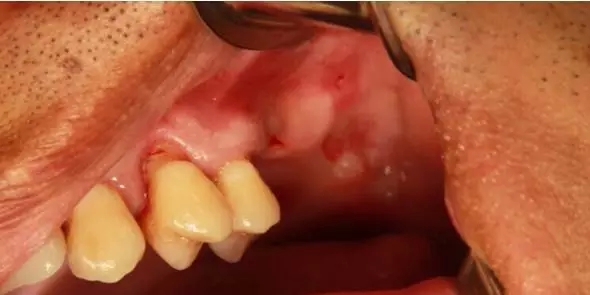

患者50歲,男性,身體健康。左上6,7缺失,骨高度2mm。

術(shù)前口內(nèi)照和CT片。

因?yàn)?,5根方要取骨,所以切口設(shè)計(jì)在4的近中。